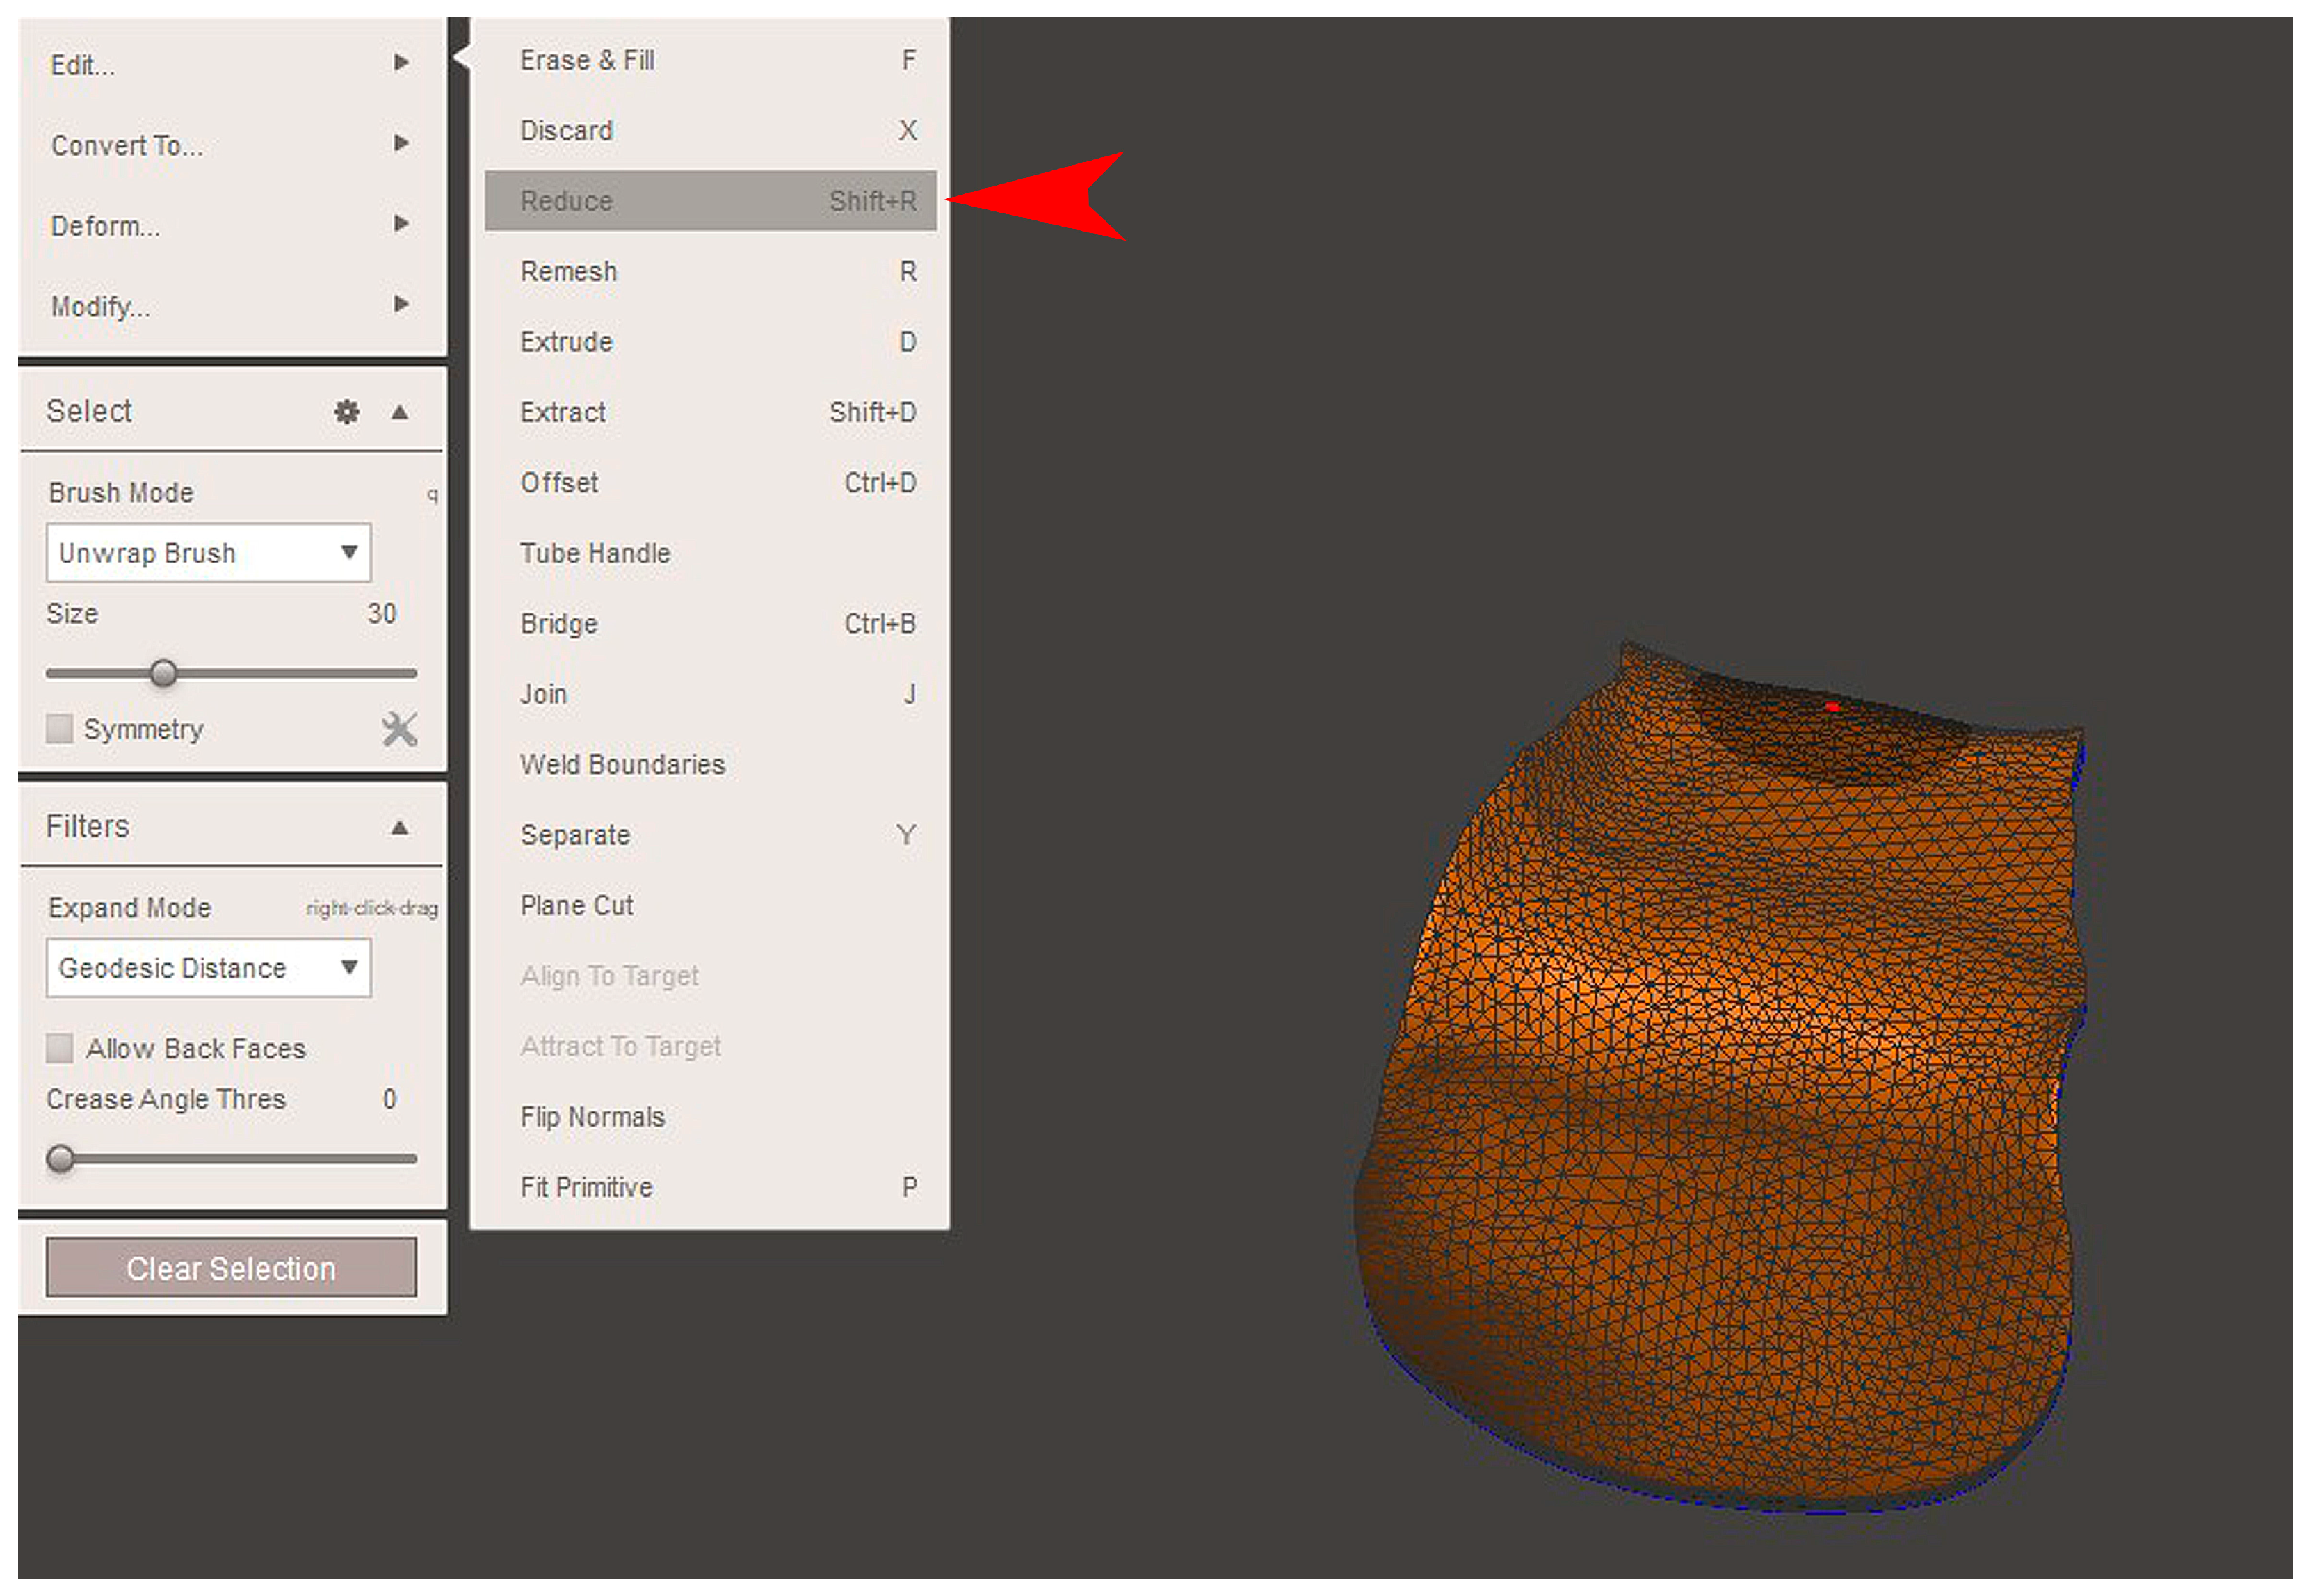

2.2. GBR Simulation and Mesh Design